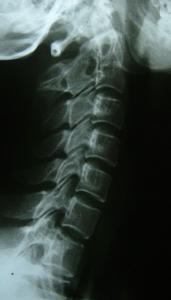

先進設備:先進的X光機全自動生化檢驗儀,關節鏡和椎間盤鏡,手術室安裝了層流消毒設備醫院電腦化管理系統等。

正骨醫院堅持中醫骨科特色,以中醫為主,中西醫結合治療各種骨傷、骨病、對跌打損傷、骨折、關節脫位、股骨頭壞死、骨結核、骨髓炎、脊椎病、風濕關節炎等有豐富的臨床經驗,療效獨特。同時,不斷開展骨科新項目,如肌腱轉移延長術、島狀皮瓣術、人工關節置換術(肩、肘、髖、膝)、小兒麻痹矯治術、脊椎減壓及內固定術、顯微斷肢再植術等。康復理療科目前開展有理療、按摩、針炙等項目,並擁有各種不同的理療設備25台(包括超雷射治療儀、干擾電治療儀、微電腦牽引床、骨質疏鬆治療儀等先進設備),對各種他傷後期康復、風濕性關節炎、退行性病變、腰腿痛、頸椎病等有良好療效,深受病患者歡迎,2001年日均治療量達343人次。